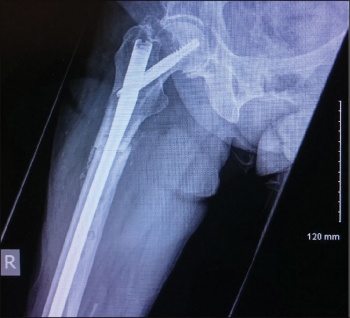

An 83-year-old woman presented to hospital with low energy trauma resulting in non-weight bearing and pain in her right thigh. She had chronic obstructive pulmonary disease (COPD), diabetes mellitus type 2, gastroesophageal reflux disease (GERD) and osteoporosis. She had a right neck of femur intertrochanteric fracture in 2010 for which she had a two-hole dynamic hip screw (DHS) plate.

She was started on alendronate therapy in 2011 for osteoporosis. She had left distal radius fracture in 2013 for which she had manipulation under anaesthesia and k-wiring. She had a low energy trauma in January 2015 and was brought in with right thigh pain and non-weight bearing.

She had an x-ray right femur and pelvis showing an atypical right femur sub-trochanteric fracture. She was taken to the theatre the next day and her two-hole plate was removed without taking the lag screw and was replaced with an eight-hole DHS plate. She was started on physiotherapy and within a few weeks she was walking with a walking frame. She was followed up with regular x-ray. Her alendronate was stopped and she started on teriparatide injections. Teriparatide is a man-made form of the hormone parathyroid which exists naturally in the body.

Figure 1. DHS two-hold plate for neck of femur fracture(click to enlarge)